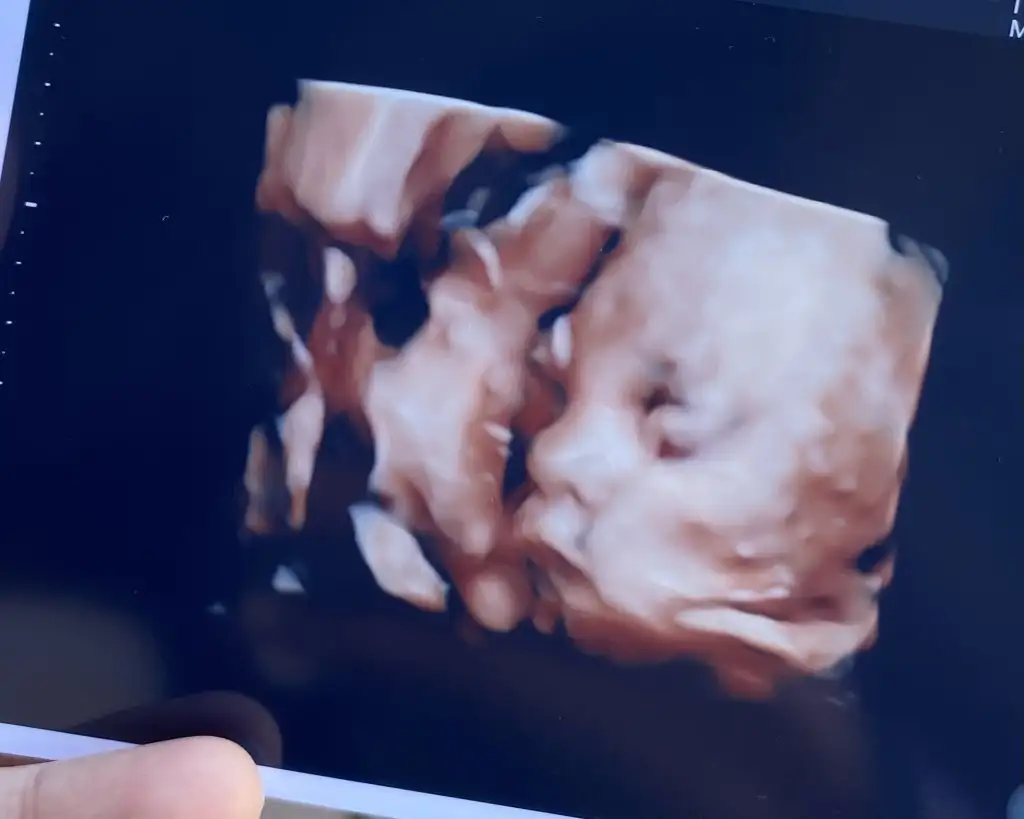

Galiba sisteme bizim sat giriyorlar ona göre hesaplanıyor oKizlar bugun bizim de kontrol vardi. Ben uygulamadan 30+3 diye görüyorum hatta dr'un ciktisinda da 30w3d yazio ama dr bana 28.29 haftada gibisin dedi bizim kontrollerimiz sonucunda. Bebek 1kilo 313 gram ve 38 cm imis. Normal dedi. 20-22 ocak gibi dogum olur dedi sezeryan dedim ben. Yaklasik 50 cm ve 3300 kg dogar dedi. Benm anlamadığım neden kagitta yazan 30+3 sun demiyo? Resmini de attim oğlanın:)

Canim sat giriyor cihaza ondan oyleKizlar bugun bizim de kontrol vardi. Ben uygulamadan 30+3 diye görüyorum hatta dr'un ciktisinda da 30w3d yazio ama dr bana 28.29 haftada gibisin dedi bizim kontrollerimiz sonucunda. Bebek 1kilo 313 gram ve 38 cm imis. Normal dedi. 20-22 ocak gibi dogum olur dedi sezeryan dedim ben. Yaklasik 50 cm ve 3300 kg dogar dedi. Benm anlamadığım neden kagitta yazan 30+3 sun demiyo? Resmini de attim oğlanın:)

Kağıtta yazan sat tarihine göre günün oluyor diye biliyorum canım, yandaki diğer ölçümlerde bebeğin uyumlu olduğu hafta yazıyor olması lazım onlarda 28 29 mu yazıyordu.Kizlar bugun bizim de kontrol vardi. Ben uygulamadan 30+3 diye görüyorum hatta dr'un ciktisinda da 30w3d yazio ama dr bana 28.29 haftada gibisin dedi bizim kontrollerimiz sonucunda. Bebek 1kilo 313 gram ve 38 cm imis. Normal dedi. 20-22 ocak gibi dogum olur dedi sezeryan dedim ben. Yaklasik 50 cm ve 3300 kg dogar dedi. Benm anlamadığım neden kagitta yazan 30+3 sun demiyo? Resmini de attim oğlanın:)

Maşallah canım çok yakışıklı olucakKizlar bugun bizim de kontrol vardi. Ben uygulamadan 30+3 diye görüyorum hatta dr'un ciktisinda da 30w3d yazio ama dr bana 28.29 haftada gibisin dedi bizim kontrollerimiz sonucunda. Bebek 1kilo 313 gram ve 38 cm imis. Normal dedi. 20-22 ocak gibi dogum olur dedi sezeryan dedim ben. Yaklasik 50 cm ve 3300 kg dogar dedi. Benm anlamadığım neden kagitta yazan 30+3 sun demiyo? Resmini de attim oğlanın:)

Bizimkinin 29 haftalık fotisişuan 31 haftalık olduk. Valla yüzünü o kadar zor gördük ki bir saat sürekli çikolata yiyip tekrar baktık.. Pipisini görmesek kız olduguna inanıcam